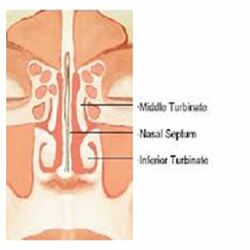

Concha Bullosa

Conchae are structures made of bone inside of your nose. They help control the airflow into your nose, besides cleaning and warming air that is inhaled so that it’s ready for respiration.

Concha bullosa happens when one of the conchae, or turbinates, inside your nose becomes filled with a pocket of air. This is also known as pneumatization of the turbinate.

There are three pairs of conchae in your nose on either side of the septum. Your septum is the structure that divides your nose in half.

These conchae include:

- The superior turbinates, which are the highest conchae in your nose, near your brain. These protect the olfactory bulb, the part of your brain that helps you smell.

- The middle turbinates, which sit between the superior and inferior conchae. They help keep inhaled air from going directly into your sinuses.

- The inferior turbinates, which are the lowest conchae in your nose. They help moisturize and warm up inhaled air before it goes into your lungs.

You may notice some pain or discomfort around your sinuses when the middle turbinates get filled with an air pocket. The most common symptoms include:

- Pressure or pain around your sinuses and the area around your eyes

- Feeling like you can’t get enough air in or out of your nose

- Feeling that something is in the way inside your nostrils